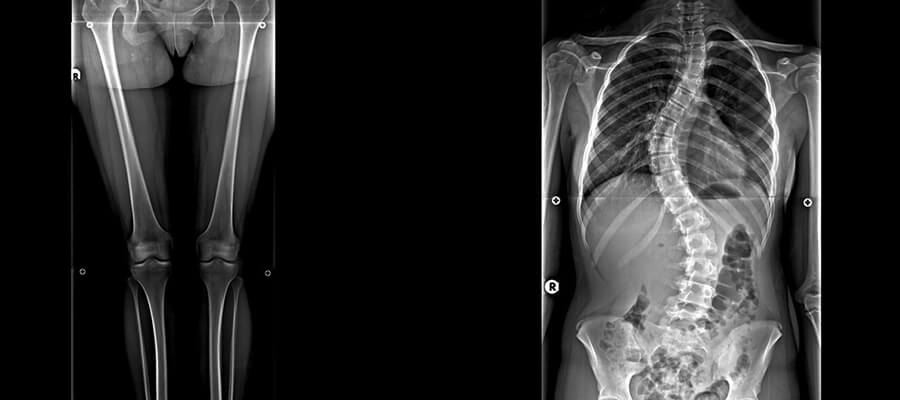

Ortoröntgenogram, orta yaş grubunun ve gençlerin sıklıkla karşılaştığı skolyoz rahatsızlığının erken dönemde teşhisini koyabilmek adına hastalara mutlaka uygulanması gerekir. Skolyoz rahatsızlığı oldukça zorlu ve ağrılı bir şekilde geçmektedir.

Aslında ortoröntgenogram skolyoz grafisi olarak da bilinir. Özel çekim olarak gerçekleştirilir ve röntgen uygulaması altında gerçekleştirilmiş olur.

Günümüz şartlarında gelişmekte olan teknolojiyle birlikte sağlık alanında tanı ve tedavi için cihazlarda gelişmiştir. Bu cihaz yardımıyla elde edilen görüntülerde skolyozun ölçüleri alınır. Skolyoz açısının doğru şekilde belirlenebilmesi ise oldukça önemlidir.

Skolyoz rahatsızlığında net görüntülerin elde edilebilir olması ve 3 boyutlu şekilde görüntülenmesi için ortoröntgenogram çekiminden yardım alınır. Çekilecek olan film üç farklı yönden belirlendikten sonra çekilir. Skolyozun eğriliğini ve doğru açısını belirleyerek ölçümler alınır. Boyundan başlayarak kalçaya kadar uzanan bir kemik yapısına sahip olduğu için çekim işlemleri gerçekleştirilir.

Skolyoz rahatsızlığı, bel kemiğinde ortaya çıkan eğrilik anlamına gelir. Yani sağlıklı veya normal koşullarda bel kemiğinin düz bir yapıya sahip olması gerekiyor. Eğrilik sorunları genelde bel kemiğinin sağ tarafa veya sol tarafa sapmasından kaynaklıdır.